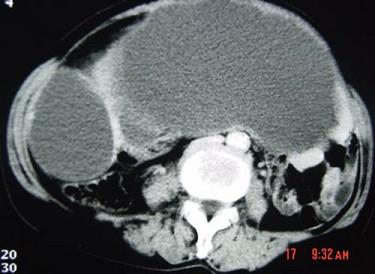

问题 55岁女性患者,腹胀腹痛消瘦一年余,行CT扫描如图所示,你认为最佳答案是 ( )

选项 A、卵巢浆液性囊腺瘤 B、卵巢囊腺癌 C、卵巢囊肿 D、卵巢粘液性囊腺瘤 E、卵巢表皮样囊肿

答案 B